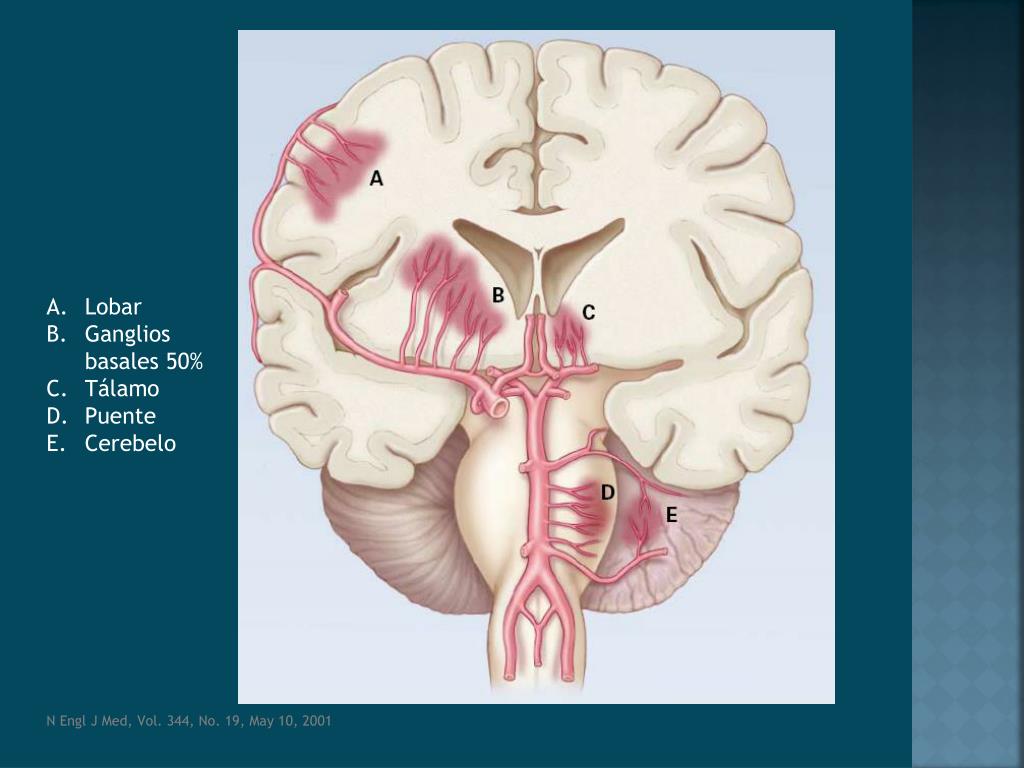

10. Lobar Ganglios basales 50% Tálamo Puente Cerebelo N Engl J Med, Vol. 344, No. 19, May 10, 2001

9. Hemorragia intracerebral primaria • HTA crónica y cambios degenerativos de las arterias cerebrales • Sitios más comunes • Putamen y Cápsula interna • Sustancia blanca central de lóbulos temporales, parietales o frontales (hemorragias lobares) • Tálamo • Puente • Cerebelo • Arteria penetrante q se origina de un territorio vascular mas grande Principios de Neurología, 8va edición. 2007, Adams